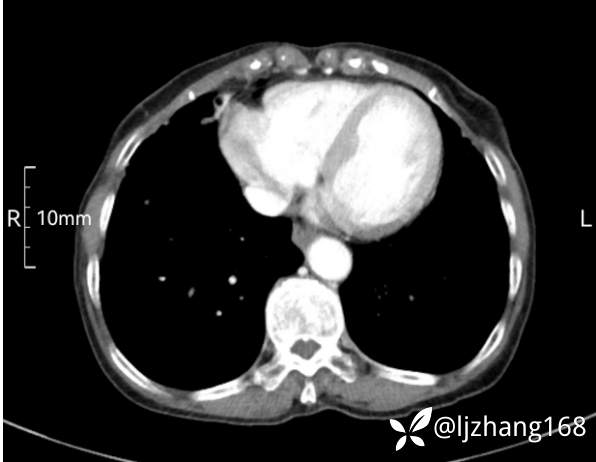

74岁女患,反复咳嗽2月,右肺空洞性病变,炎症OR肿瘤(有病理)

简要病史:2月前开始受凉后出现咳嗽,咳少许白色粘液痰,痰不易咳出,无痰中带血及咯血,无畏寒发热,外院胸部CT提示右下肺空洞病变,脓肿可能性大,常规抗感染治疗效果不佳。既往否认“糖尿病”等病史,有高血压基础病史,无吸烟史。

辅助检查:胸部CT右肺下叶前基底段结节并空洞

临床诊断:右肺空洞:脓肿?